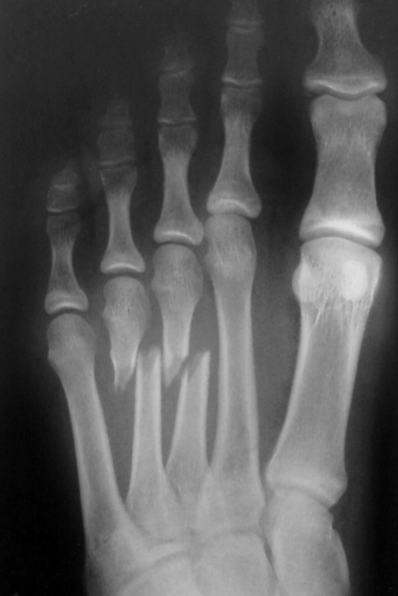

Stress Fracture

Stress fracture –

gradually develops

from multiple

repetitions of force